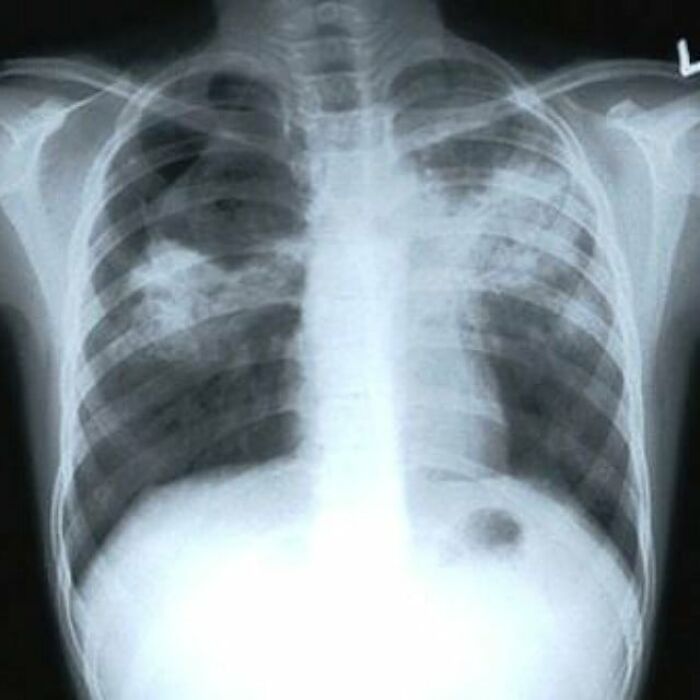

#67 Active Pulmonary Tb, Infiltrates Or Consolidations And/Or Cavities Are Often Seen In The Upper Lungs With Or Without Mediastinal Or Hilar Lymphadenopathy

Image source: medical_pedia